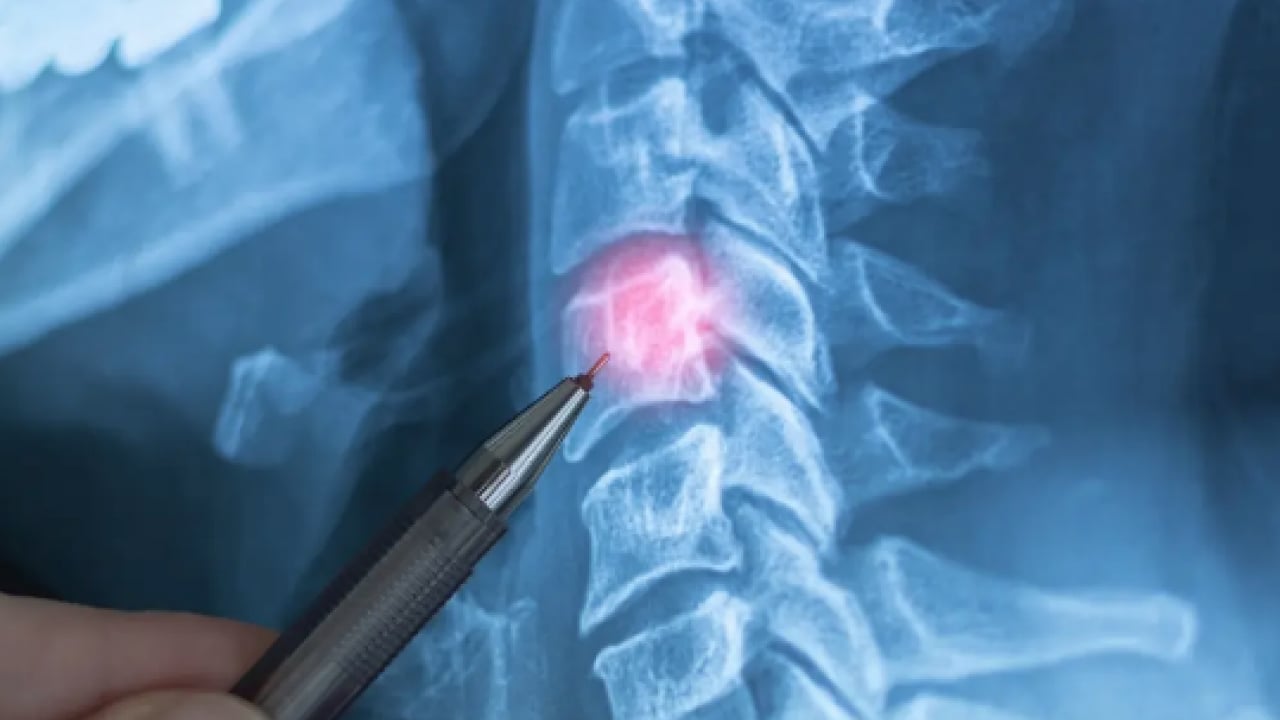

Boyun ve bel fıtığı neden olur? Uzmanından o hatalar fıtığı tetikliyor uyarısı

Boyun ve bel fıtığı neden olur sorusunu Dr. Erkan Kutlu Ekiz açıkladı. Özellikle masa başı iş alanında, uzun süre telefon kullananlarda ortaya çıkıyor.

Boyun ve bel fıtığı, günümüzde özellikle masa başı çalışanlar, uzun süre telefon kullananlar ve hareketsiz yaşam sürenlerde giderek daha sık görülüyor. Akşam'a göre; Peki fıtık ağrısı nasıl anlaşılır, hangi belirtiler ihmal edilmemeli ve ameliyat her zaman gerekli mi?

Geçmeyen boyun ağrısı, kola vuran uyuşma, belde batma hissi ya da bacakta güç kaybı... Birçok kişi bu şikâyetleri "yorgunluk" sanıp erteliyor, ancak uzmanlara göre bu belirtiler boyun ve bel fıtığının erken sinyalleri olabilir. Tanıdan tedaviye, egzersizden günlük alışkanlıklara kadar en çok merak edilenleri Dr. Erkan Kutlu Ekiz, Sena Parlar'a açıkladı...

Bel ve boyun ağrıları, modern yaşamın en yaygın sağlık sorunları arasında yer alıyor. Ancak her ağrı fıtık anlamına gelmediği gibi, her fıtık da ameliyat gerektirmiyor. Bu röportajda; boyun fıtığı belirtileri, bel fıtığı tedavisi, doğru duruş, fizik tedavinin etkisi ve "ne zaman doktora gidilmeli?" sorularına uzman görüşleriyle yanıt aradık.